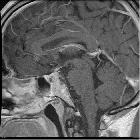

MRI

A stalk-like connection to the clivus is usually seen if high-resolution images are obtained.

Apart from the characteristic location (retroclival, prepontine, and intradural), MRI findings are non-specific, with signal similar to CSF:

- T1: hypointense

- T2: hyperintense

- T1 C+ (Gd): variable, however, most cases have not shown substantial enhancement